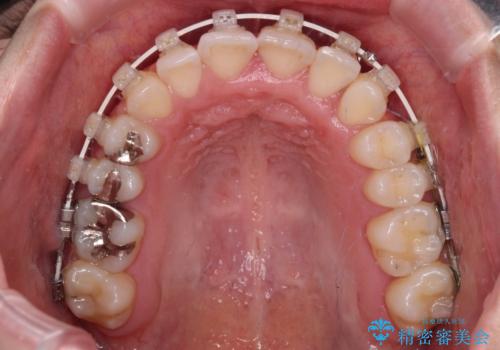

歯列矯正では基本的に骨格を改善することはできませんが、急速拡大装置(MARPE)を使用することで上顎骨を側方に拡大させることができ、咬合状態を大きく改善することができます。

事前に急速拡大装置で側方拡大を行い、上下を目立たないワイヤー装置により歯列を整えていくこととしました。

急速拡大装置により骨格はある程度改善されましたが、奥歯の咬み合わせ改善に非常に時間がかかってしまいました。